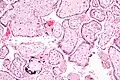

![]() Micrografía de citomegalovirus (CMV) infección de la placenta (placentitis CMV), una infección de transmisión vertical: El característico gran núcleo de una célula infectada con CMV se ve descentrada en la parte inferior derecha de la imagen, tinción H&E. | ||

Además de infectar al feto, los patógenos transplacentarios pueden causar placentitis (inflamación de la placenta) y/o corioamnionitis (inflamación de las membranas fetales).

Placentitis por citomegalovirus (CMV) -

Placentitis por citomegalovirus (CMV)